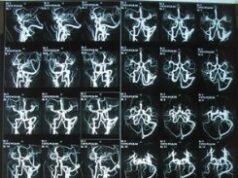

Что показывает МРТ сосудов головного мозга?

Осуществление сканирования головного мозга МРТ методом считается наиболее достоверным и совершенно безопасным способом. В момент проведения данной процедуры все отклонения...